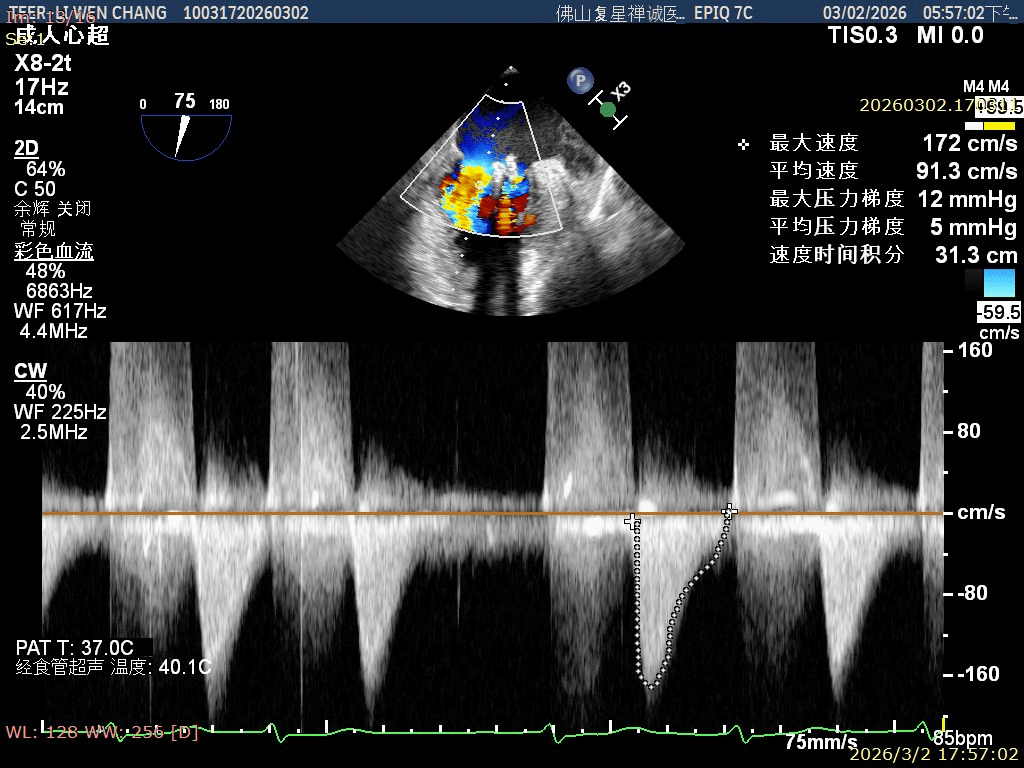

术前影像

X-plane1区 反流重度

彭宇程教授团队行房间隔穿刺,高度4.3cm,依次置入导引鞘和XW0612瓣膜夹,瓣上精准调整测试瓣膜夹Position、Orientation、Trajectory,跨瓣后打开瓣膜夹捕捞,确认前后瓣叶平铺在夹臂上,Gripper down后,慢慢关闭瓣膜夹夹臂,释放前后都进行评估,确认夹子内外两侧仍存在少量反流,决定在第一枚夹子外侧补放一枚SN0409瓣膜夹,瓣膜夹捕获瓣叶后,评估剩余瓣口面积,跨瓣压差,残余反流,取得优秀的效果,决定释放;术后即刻评估显示二尖瓣反流得到显著控制,跨瓣压差约5mmHg,肺静脉逆流征象明显改善,血流动力学效果优异。